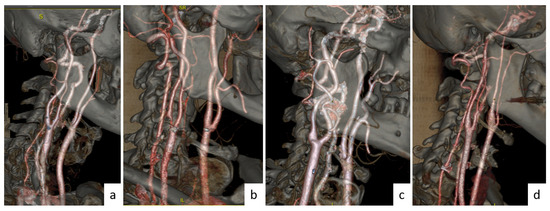

2.7. Data Collection

Figure 3. Set of 3D images of the carotid arteries obtained with AW Server software for patients: (a) normal, (b) stenosis, (c) aneurysm, and (d) dissection.